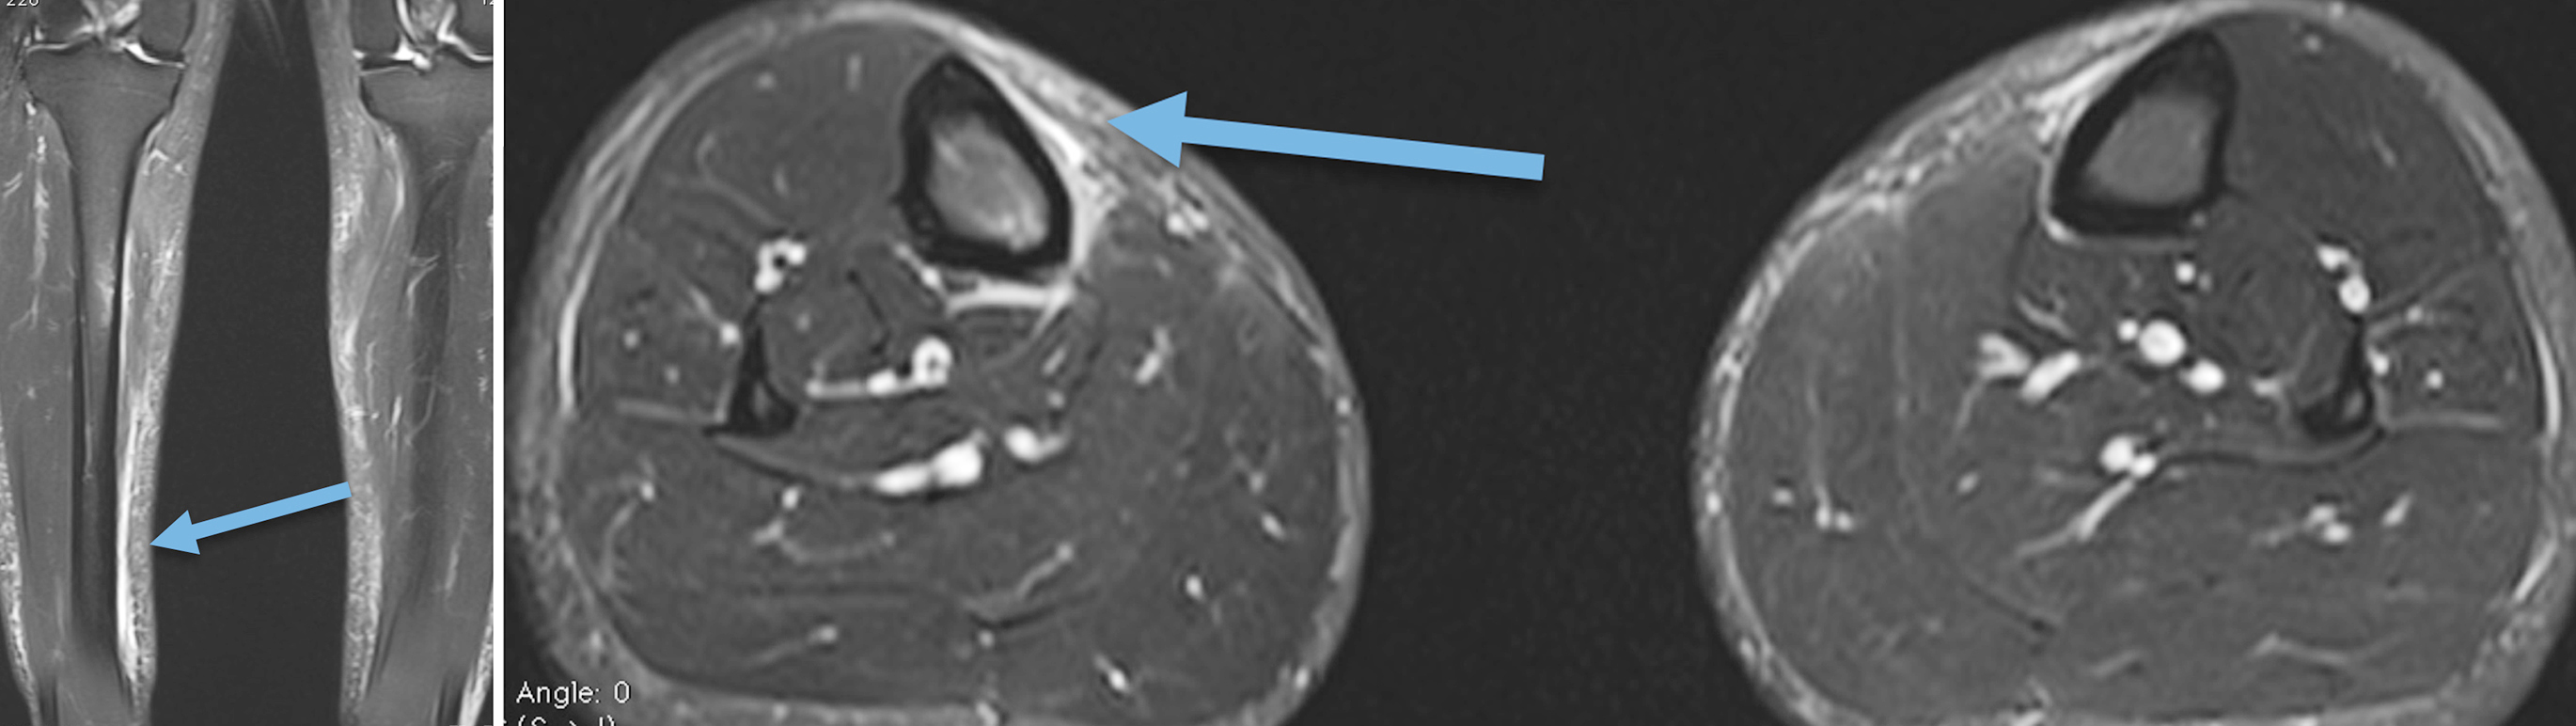

Schwannome du nerf tibial